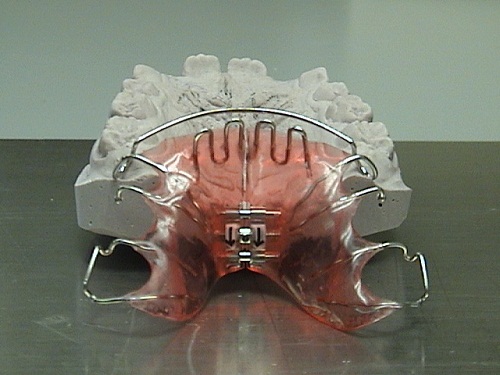

Στόχος της ορθοδοντικής θεραπείας είναι η αποκατάσταση της ανώμαλης σχέσης μεταξύ των γνάθων και των δοντιών, καθώς και των δυσμορφιών του προσώπου που πιθανόν να συνεπάγονται από τα προβλήματα. Πραγματοποιείται μέσω της μετακίνησης των δοντιών σε μια νέα επιθυμητή θέση με άσκηση συστημάτων δυνάμεων στα δόντια ή/και στα οστά μέσω των ορθοδοντικών ή/και ορθοπεδικών συσκευών.

Η Ορθοδοντική προλαμβάνει, διαγιγνώσκει και θεραπεύει τα ορθοδοντικά προβλήματα για λειτουργικούς και αισθητικούς λόγους. Παίζει σημαντικό ρόλο στη βελτίωση της στοματικής υγείας, εξασφαλίζει αρμονία μεταξύ δοντιών και προσώπου και χαρίζει ένα όμορφο και λαμπερό χαμόγελο, το οποίο βελτιώνει τη ποιότητα ζωής μας σε προσωπικό και επαγγελματικό επίπεδο αυξάνοντας την αυτοπεποίθησή μας.